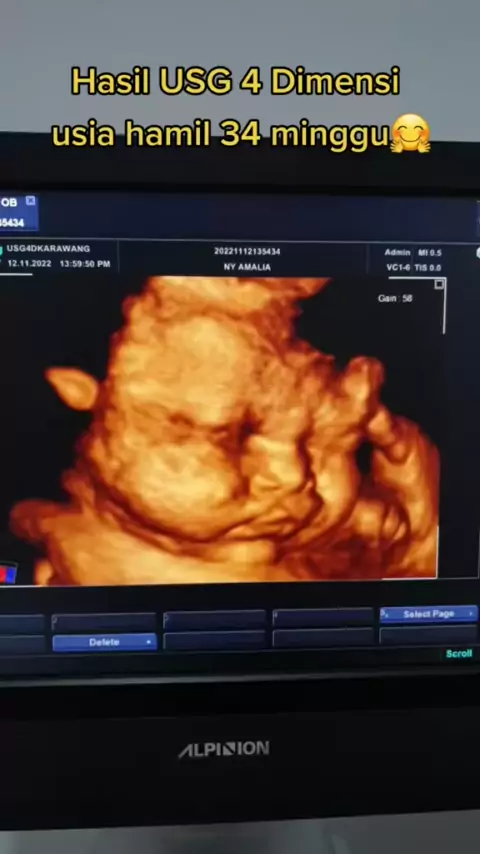

USG 4D usia kehamilan 34 minggu##viral#trending#usg4d#usg4dimensi#usg4dkarawang#usg4dimensikarawang#34weekspregnant#hpldesember#hpljanuari2023#dokterkandungan#drspogkarawang